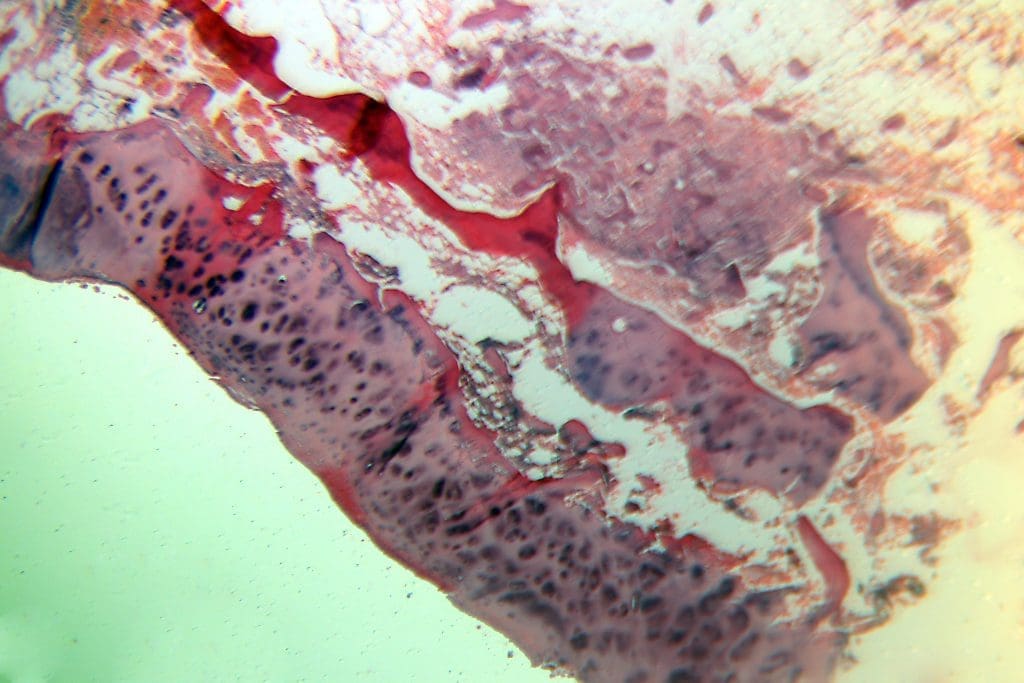

Opnames gemaakt van: bloesem margriet en van een op het microscoop aangetroffen preparaat (vermoedelijk van een stuk huid, niet nader gespecificeerd).

Gebruikte camera: Canon 77D op balg met 50 mm 1.8 objectief, omgekeerd gemonteerd